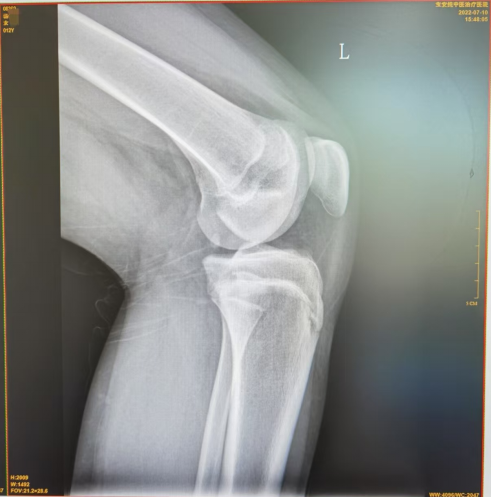

图1可见胫骨结节处无明显损伤,图2可见胫骨结节前缘舌状下缘少许分离,图3可见胫骨结节前缘舌状下缘明显分离且向前凸起。